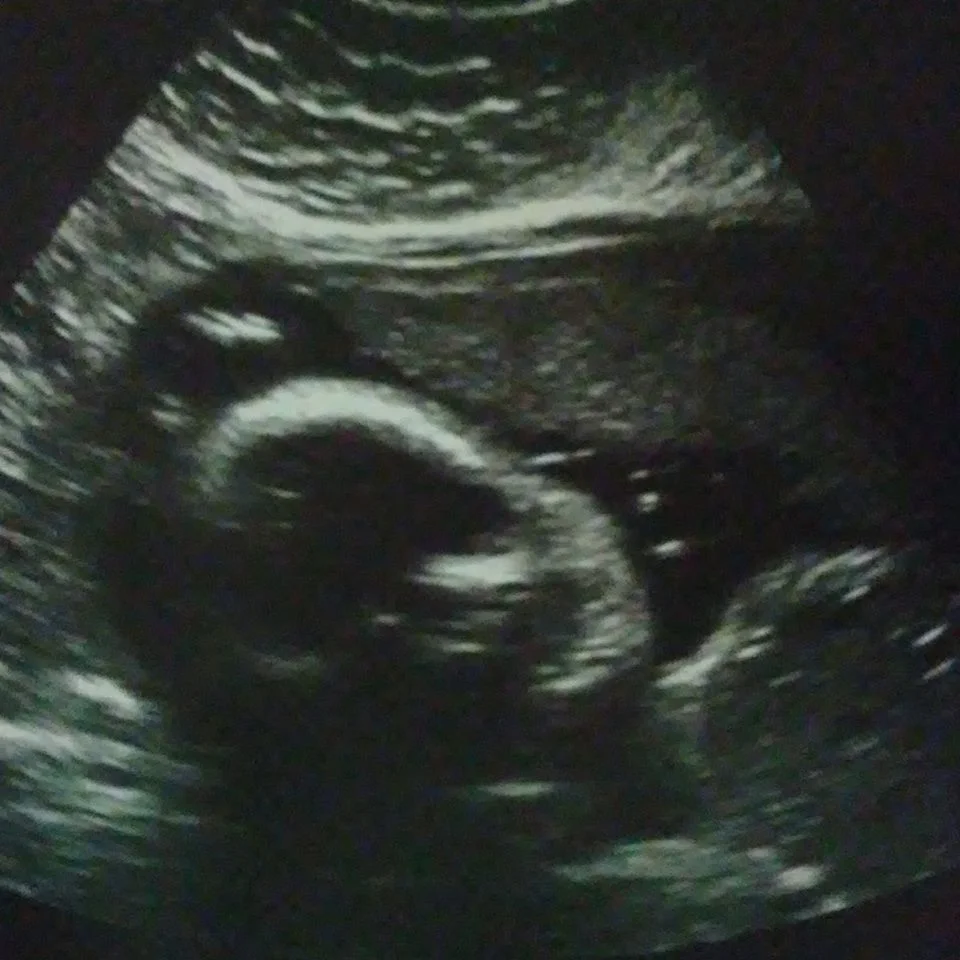

"My husband and I have a son and I'm currently pregnant with our 2nd son. During this pregnancy we got news that our baby might have Spina Bifida. My heart felt like it shattered, but we gave this pregnancy to God. I was nervous but I knew that God had this.

We went to see a specialist. As she was talking to us about everything I thought of abortion. I am pro-life but for 1 second satan put the idea in my head. I reminded myself that this pregnancy was given to God and that no matter what I would love this child that we prayed for and wanted so badly. I had 2 miscarriages prior to this pregnancy. We did our blood tests, got sonograms and finished the consultation. We prayed, we encouraged each other and we told our baby we love him.

A few days later we got a call that our baby is PERFECT and there is nothing wrong with him. Sometimes we give that 1 second of negative thinking too many more seconds and end up giving in. I am so thankful that our baby is healthy and perfectly okay. There is no way I would have been able to go through with an abortion. Feeling his kicks and hearing his heartbeat makes me feel so incredibly happy and in love." - Donyale